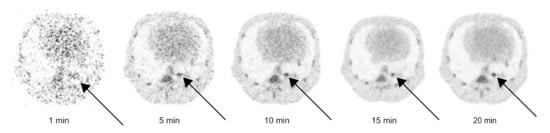

3.2.2. PET Circulation Time